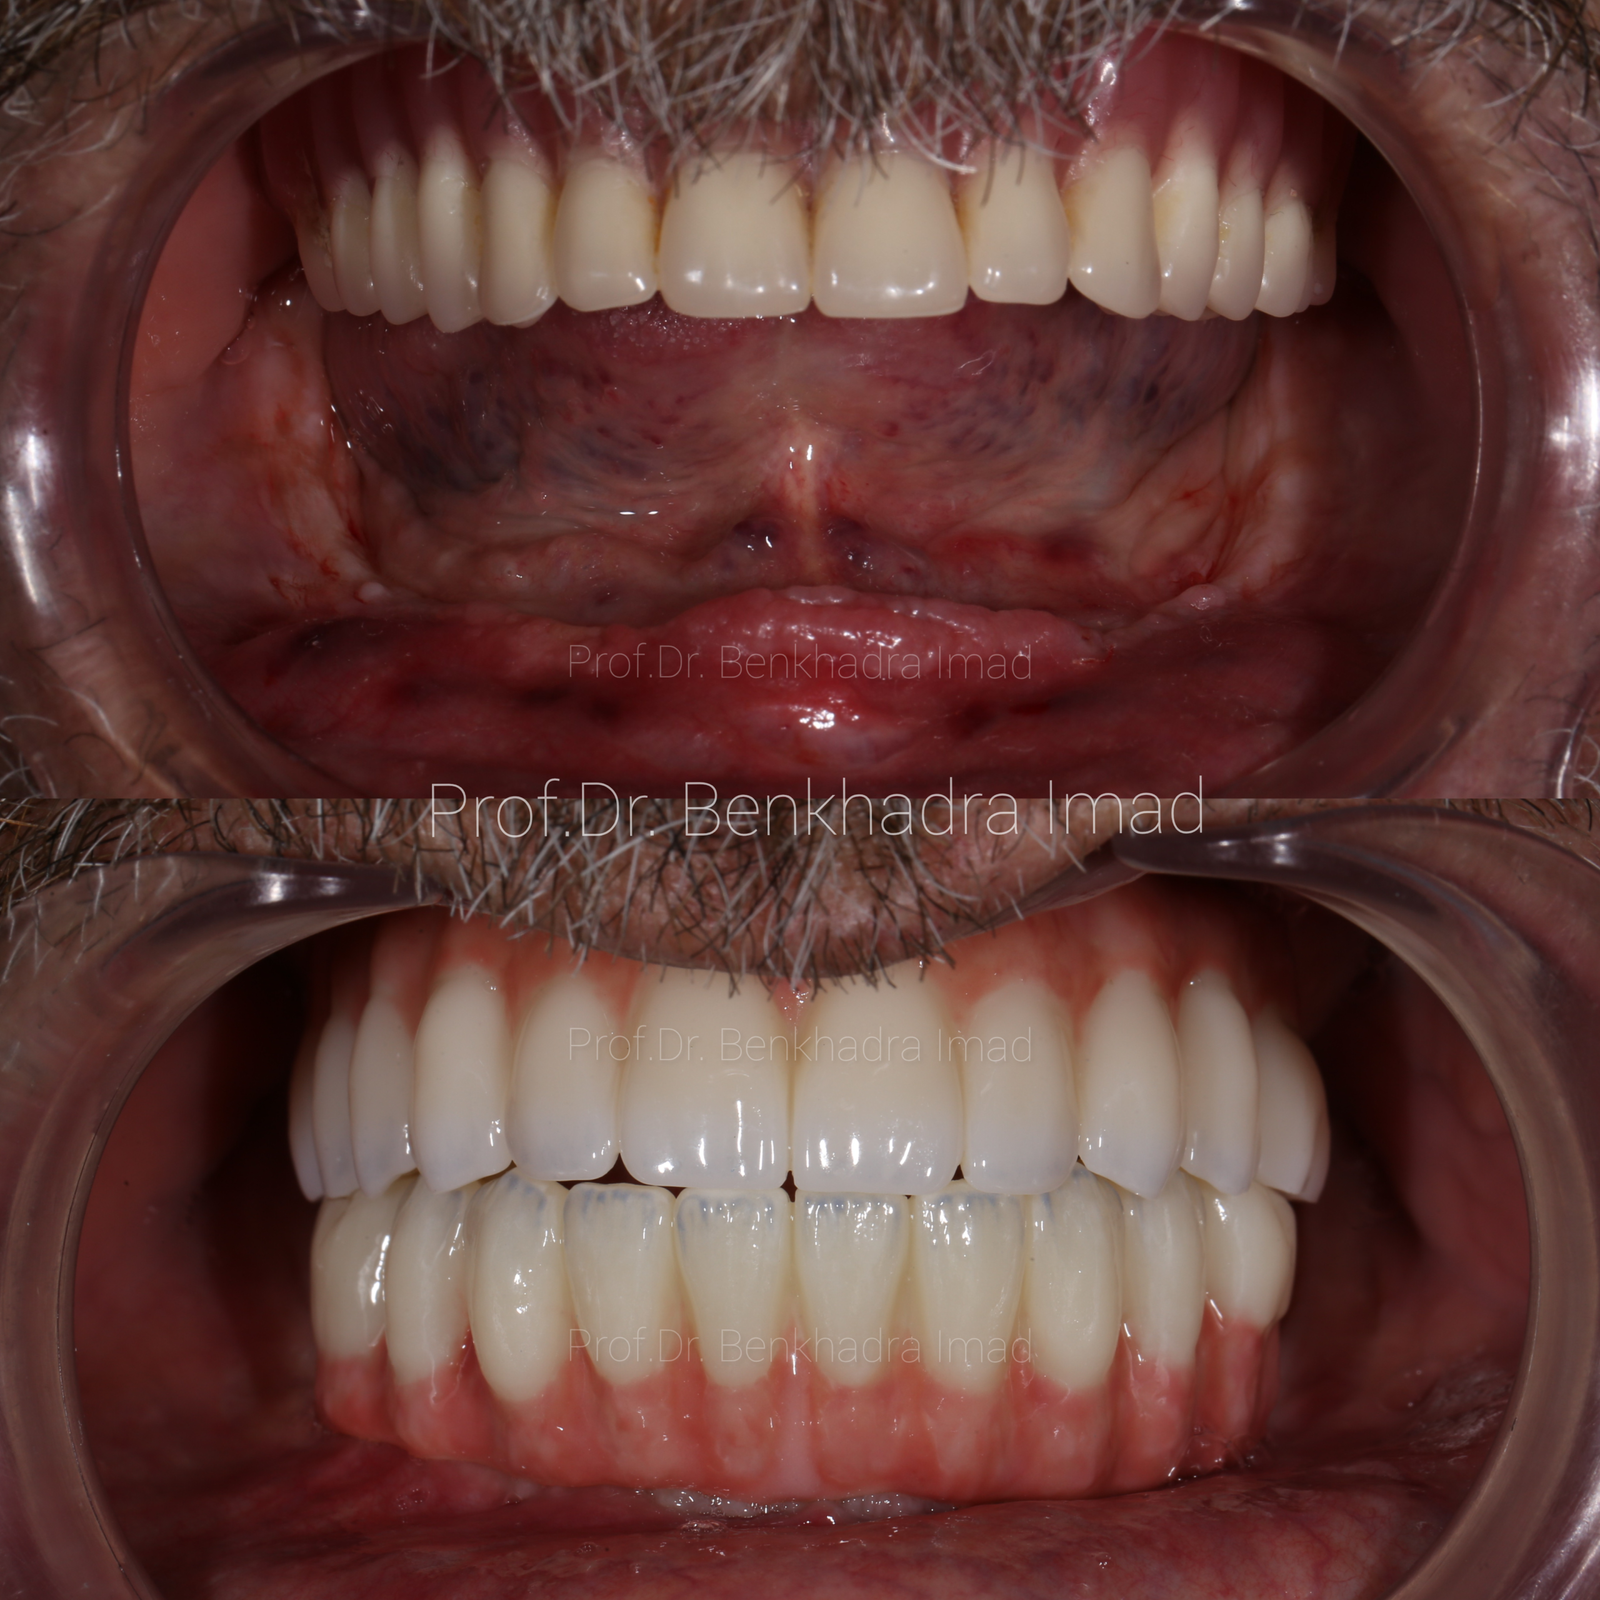

Full Smile Rehabilitation with Dental Implants | Real Case